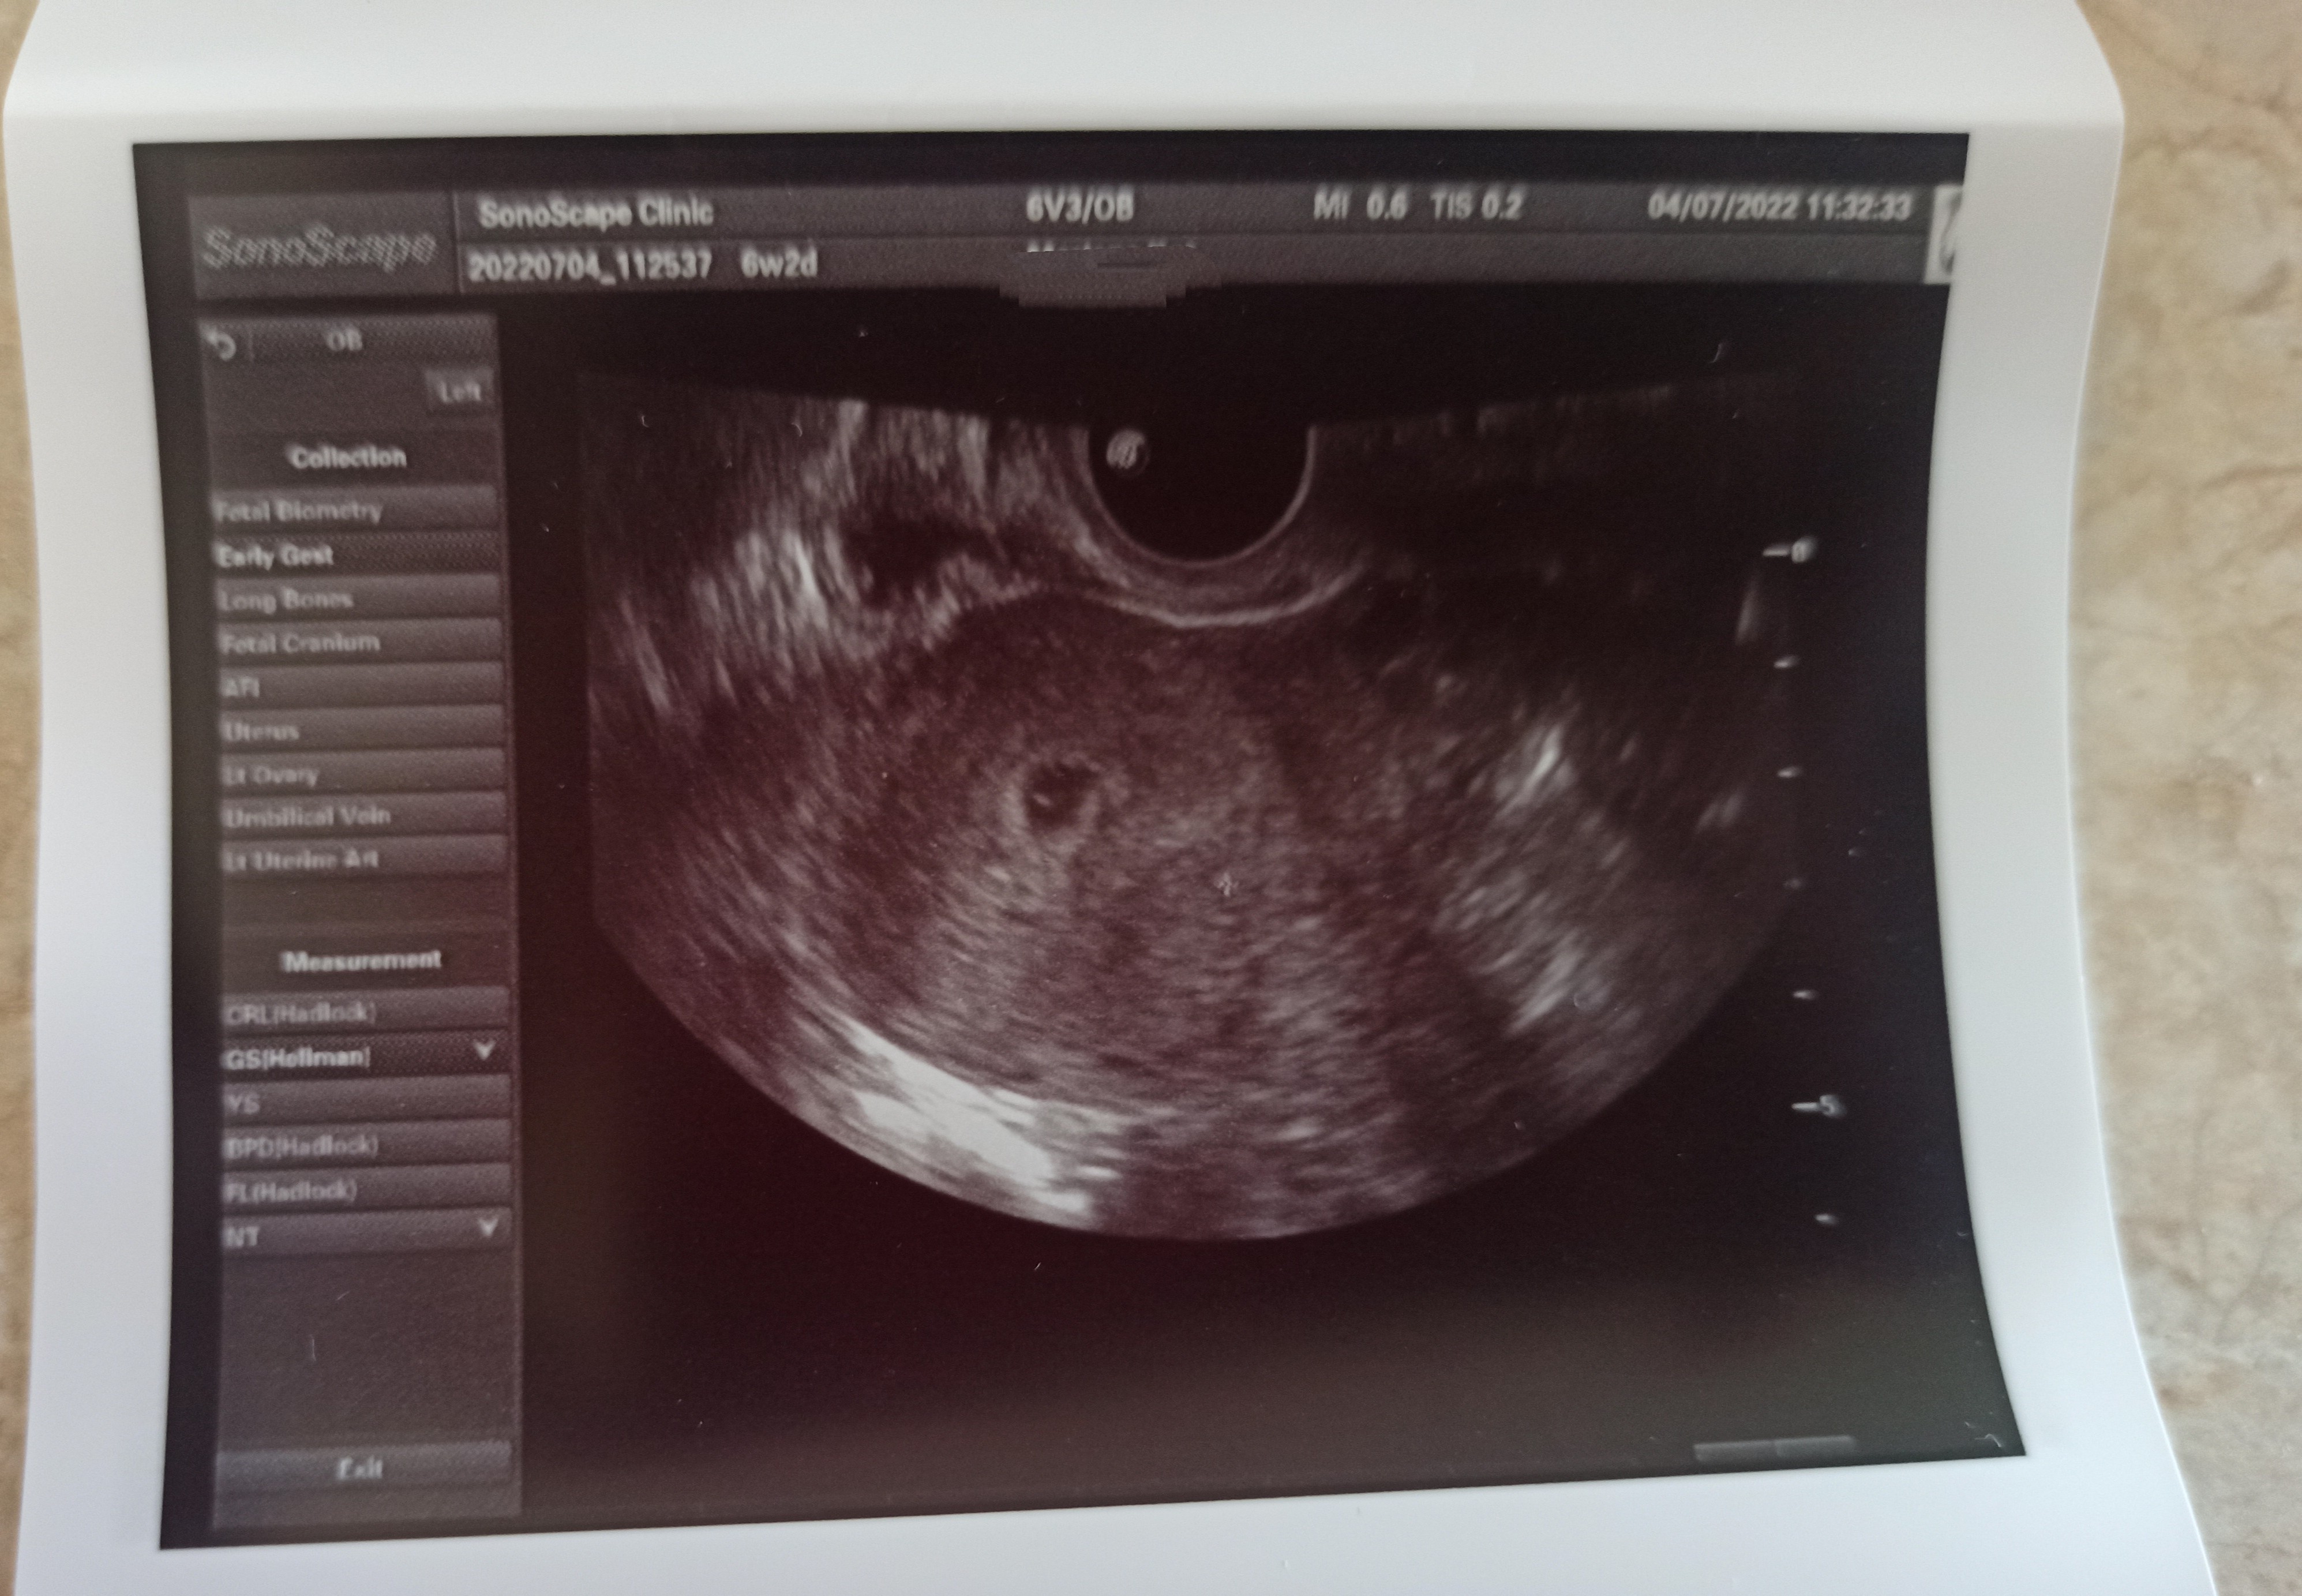

Niestety rok temu w czerwcu jak leżałam w szpitalu w ogromny upał i miałam łyżeczkowanie to mnie źle traktowali, byłam najgorsza tak jakby trędowata, mimo testu negatywnego

tylko jedna pielęgniarka przyszła się spytać jak się czuje, czy boli. Lekarze każdy mi kazania prawił na temat covid, co mnie jeszcze bardziej dobijało, bo byłam tam z innego powodu